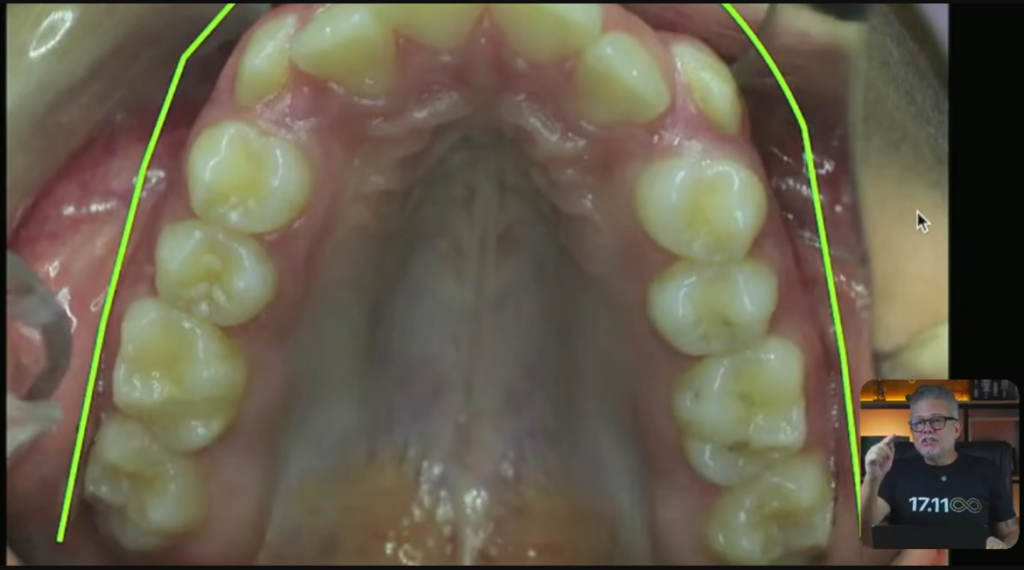

Então, essa nossa paciente, ela tem todo esse apinhamento.

Vocês estão vendo que ela está de classe 1, do lado direito e do lado esquerdo?

Quando você tem uma paciente de classe 1 dos dois lados e você tem bastante apinhamento, você pode até pensar em tirar pré-molares.

Imagina que é um expansor:

Esse expansor aqui, ele faz uma força nos pré e também nos pré do outro lado:

Então, esse verdinho que você está vendo aqui, ele vai fazer esse tipo de movimento:

Esses pré vão expandir desse jeito que você acabou de ver. Muito mais na região dos pré do que dos molares, tá?

Vai acontecer uma expansão nessa região.

E na ortopedia, a gente também coloca um negócio chamado mola frontal. Ela encosta no lateral e ela leva esse lateralzinho para vestibular:

Eu posso muito bem pegar o diagrama ortodôntico do meu paciente e fazer com que esse diagrama fique mais ou menos com esse formato: